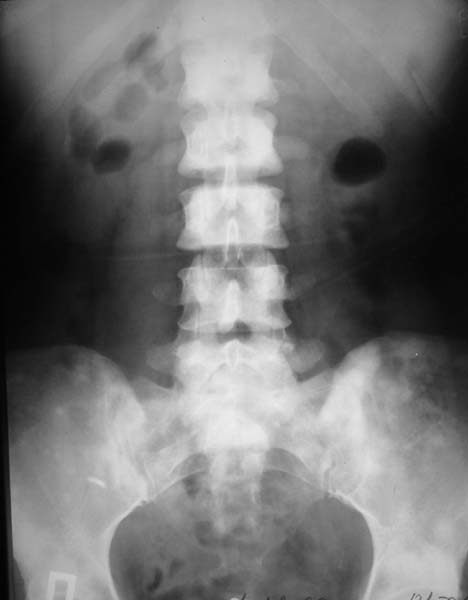

Женщина, 46 лет.

В течение четырех месяцев жалобы на боли в спине.

При МРТ (29.10.06) обнаружены диффузно-очаговые изменения в пояснично-крестцовом отделе позвоночника предположительно вторичного характера.

Остеосцинтиграфия 4.12.06. - активный остеобластический процесс в поясничном, нижнегрудном отделах позвоночника, костях таза.Местными онкологами онко-процесс исключен. Фтизиатрический и онкогематологический диагнозы исключены.